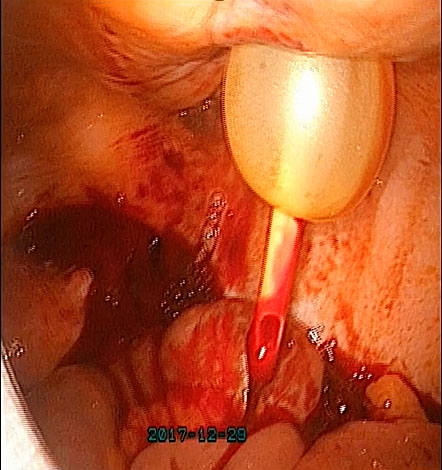

In the event of uterine artery bleeding during dissection, once identified, the laparoscopist should remain calm. CO₂ insufflation and suction at pressures below 300 mmHg help maintain pneumoperitoneum. The bleeding vessel should be carefully grasped with bipolar cautery forceps or another appropriate instrument (Figure 17) after adequate dissection. Occasionally, the presence of a gauze piece can help localize the bleeding source. It is important to avoid forcefully grasping the bleeding area, as the uterine artery lies above the ureter, which in turn is above the uterine vein. If the bleeding originates from the vein, bipolar cautery may inadvertently damage the ureter. Once hemostasis is achieved, hemostatic agents such as Surgicel may be applied, although they are often unnecessary.

(a) |

(b) |

(c) |

17

(a) Right uterine artery active bleeding after removal of the uterus. (b) Stabilizing the bleeder by atraumatic forceps with suction. (c) Stabilized tip of the vessel coagulated with bipolar cautery forceps.